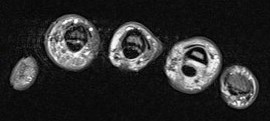

37 y/o male 4th finger injury with pain.

Annular pulley tears result in bowstringing of the tendon. Compare the sagittals of the 4th finger with the sagittal of the 5th finger which is not bowstrung (5th is labeled). I dont believe I have recognized only half of the pulley torn before.

Ulnar aspect A3 pulley tear with bowstringing of the flexor tendons